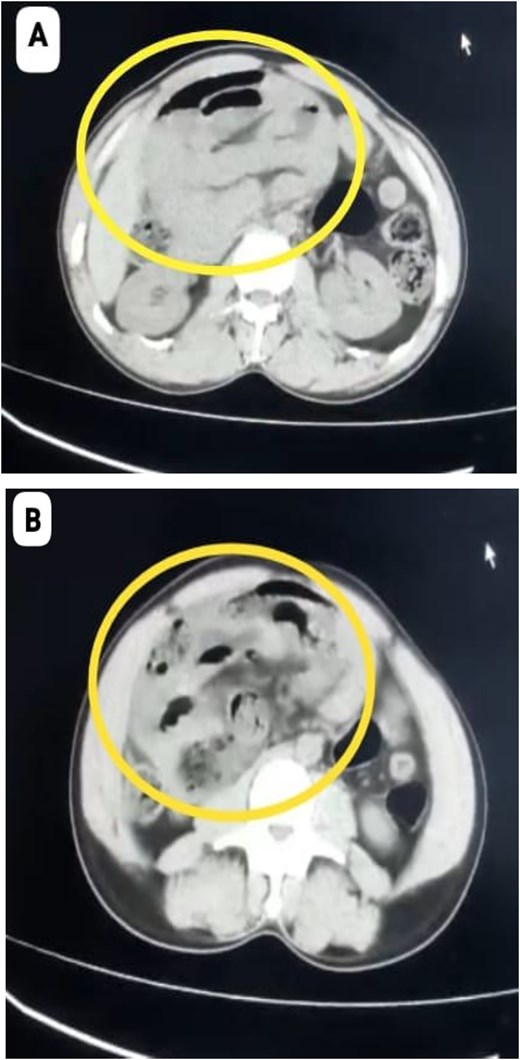

A 40-year-old male with no known comorbidities and no prior abdominal surgery presented with abdominal pain for 3 days, abdominal distention and vomiting for 1 day, along with obstipation. On admission, he was haemodynamically unstable with a blood pressure of 80/60 mmHg, pulse rate of 124 beats/min, SpO2–96% on room air. Abdominal examination revealed marked distension, diffuse tenderness with guarding and absent bowel sounds. Plain abdominal radiography demonstrated multiple dilated bowel loops with air–fluid levels, predominantly on the right side. Abdominal computed tomography (CT) revealed encapsulated clusters of jejunal and ileal loops inferior to the third part of duodenum with small bowel faeces sign. The superior mesenteric artery (SMA) and superior mesenteric vein (SMV) were seen at the neck of the sac and displaced towards left lateral side, findings consistent with right PDH causing small bowel obstruction (Fig. 1A and B).

(A, B) CT Showing cluster of small bowel loops in right upper quadrant of abdomen consistent with right paraduodenal hernia.